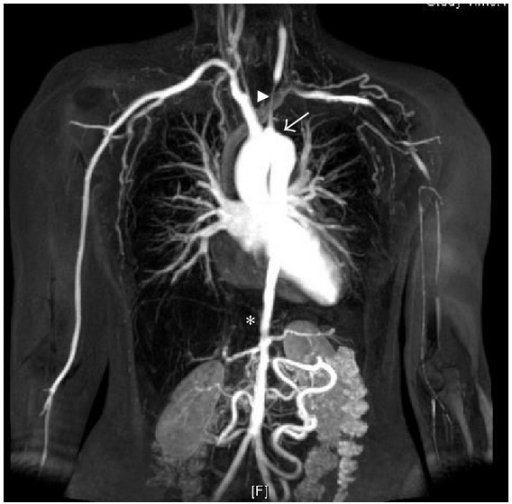

MRA of a patient with significant vascular narrowing from Takayasu Arteritis

Takayasu arteritis: criteria for surgical intervention should not be ignored. Perera AH, Mason JC, Wolfe JH - Int J Vasc Med (2013) Open Access